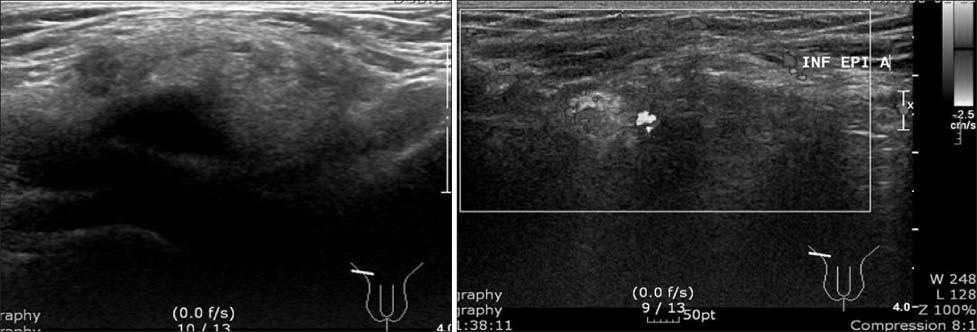

Fig. 3

Huge fatty mass encircled external iliac vein and femoral vein.

Fig. 3 Huge fatty mass encircled external iliac vein and femoral vein.